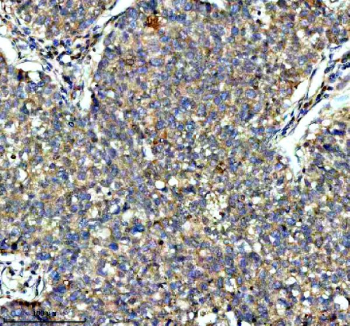

IHC analysis of KCNA6 using anti-KCNA6 antibody. KCNA6 was detected in a paraffin-embedded section of human glioma tissue. Heat mediated antigen retrieval was performed in EDTA buffer (pH 8.0, epitope retrieval solution). The tissue section was blocked with 10% goat serum. The tissue section was then incubated with 2 ug/ml rabbit anti-KCNA6 antibody overnight at 4oC. Peroxidase Conjugated Goat Anti-rabbit IgG was used as secondary antibody and incubated for 30 minutes at 37oC. The tissue section was developed using an HRP secondary and DAB substrate.